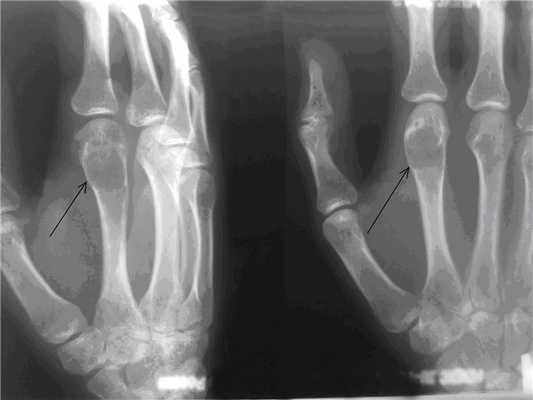

Пациентка Д., 27 лет, почувствовала острую боль и хруст в области II пястно-фалангового сустава левой кисти, когда одевала джинсы. После выполненной рентгенографии данного сегмента в лечебном учреждении по месту жительства был поставлен предварительный диагноз: хондрома II пястной кости левой кисти, патологический перелом (рис.1а). Пациентка после дообследования была госпитализирована в Клиники СамГМУ для оперативного лечения. Выполнено: экскохлеация очага, обработка образовавшейся костной полости при помощи аргоно-плазменной установки мощностью 60Вт. Аутопластика участком крыла левой подвздошной кости. Иммобилизация гипсовой лангетой 6 недель (рис. 1б). Пациентка наблюдается в условиях СОКОД в течение полутора лет.

Рис. 1. а) Рентгенограмма левой кисти в прямой и боковой проекциях больной Д. до оперативного лечения (стрелками указана энхондрома II пястной кости).

Рис. 1. б) Рентгенограмма левой кисти в прямой и боковой проекциях больной Д. после оперативного лечения спустя 3 дня, в гипсовой лонгете (стрелками указана зона экскохлеации).